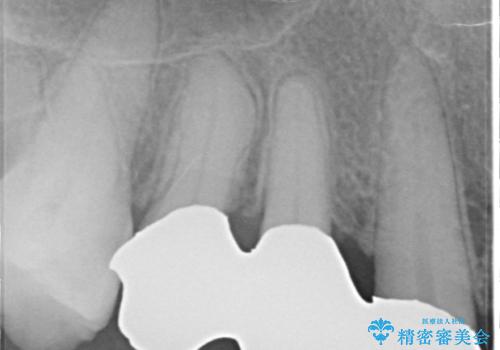

部分矯正を含む 歯周病治療 (再生治療・歯周ポケット除去・MTM・連結補綴)

検査の結果、強い歯ぎしりによる歯の周囲の骨の吸収が認められたため歯槽骨の再生・歯周ポケットの除去・力に対抗する連結補綴・補綴前処置としての小矯正を計画します。

特定の歯に強く力がかかりまた歯周病により臨床歯根が短くなっているような場合、歯の動揺を抑えるため連結補綴が検討されます。

歯の動揺が続くとより周囲の骨を失い最終的には歯を喪失してしまう可能性が高くなってしまうためです。

今回連結補綴を行うにあたり、歯周病の問題を解決するために再生療法・歯周ポケット除去手術を、またより歯の神経を保存し力に対抗できる環境を整えるために小矯正を行い精度の高いメタルボンドクラウンを製作することができました。